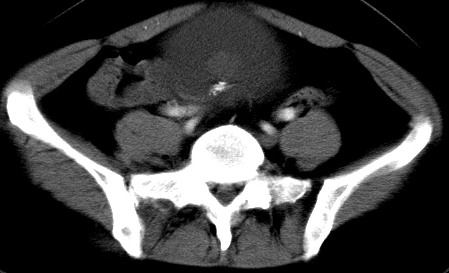

女性 病人 44岁 盆腔 下腹部痛1天!

典型的双侧附件畸胎瘤.

支持双侧附件畸胎瘤。

典型的双侧附件多发畸胎瘤!支持!